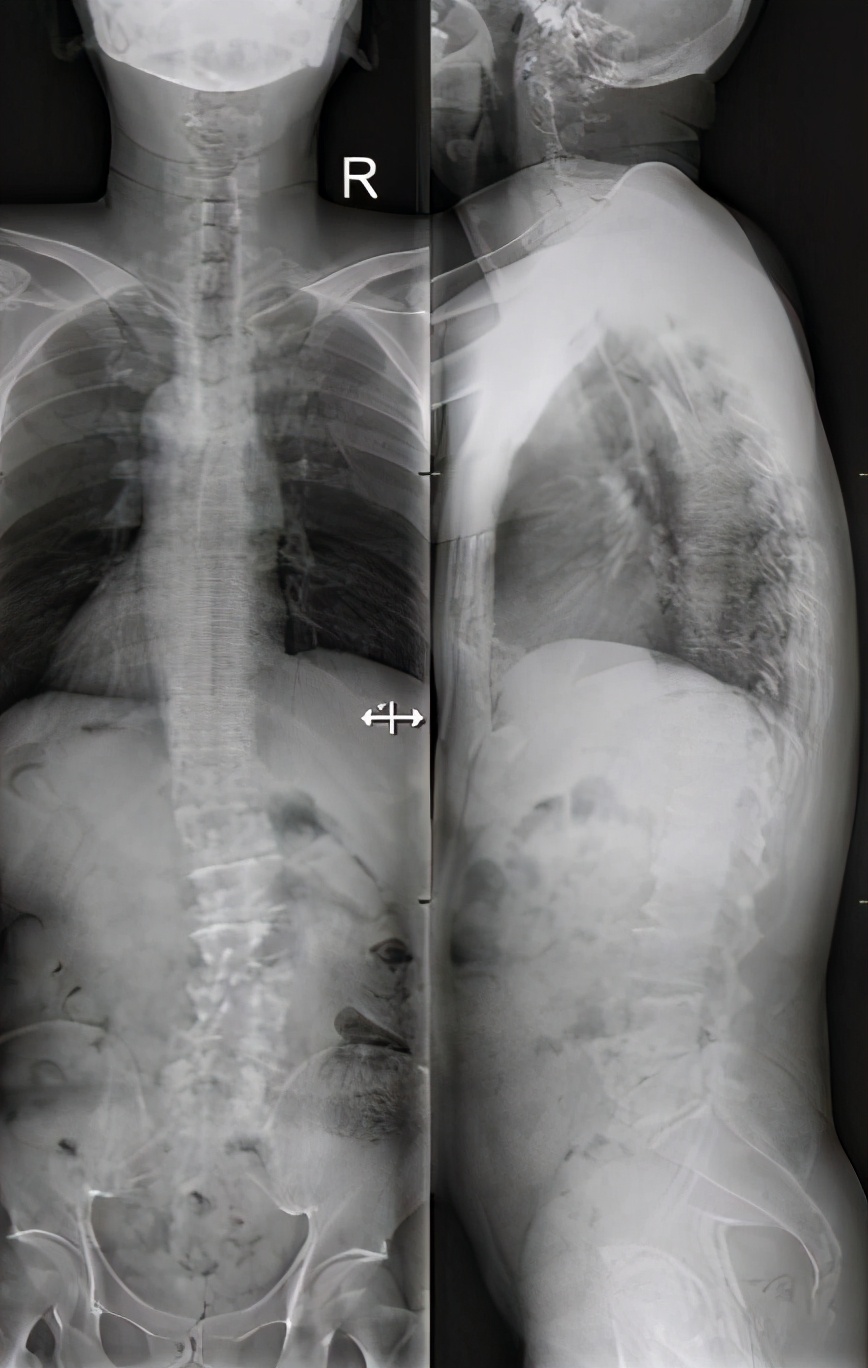

患者老年男性,因“腰痛伴有双下肢疼痛、麻木”入院,腰部疼痛为主。查体:间歇性跛行,腰背棘突及棘突间叩击痛,双下肢肌力下降。影像示:腰椎退行性变,腰椎向左侧突,椎体旋转,Cobb角为29.2°,腰椎诸椎间隙椎间高度减低,L1/2-L3/4及L5/S1椎间盘突出。患者接受胸、腰后路减压植骨融合内固定术。术后患者腰椎侧突矫正,术后Cobb角降低至10°。

患者男性,61岁,因“腰部沉重感伴双下肢疼痛、麻木2年加重2月”入院,查体:间歇性跛行,腰背棘突及棘突间叩击痛明显,左足肌力3级,右足肌力4级。影像示:腰椎退行性变,腰椎右侧突,Cobb角为26.7°,腰椎管狭窄,L4/5、L5/S1椎间盘突出。患者接受腰后路减压植骨融合内固定术。术后患者腰椎侧突矫正,术后Cobb角降低至7.8°。